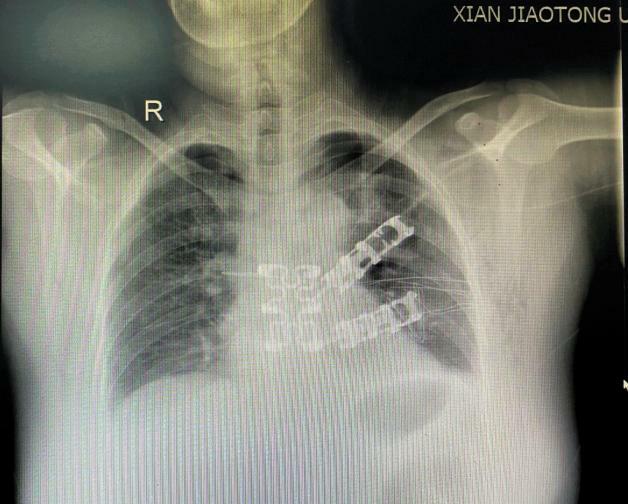

病例1:术前胸部增强CT

此位男性患者因声音嘶哑2月就诊,行胸部CT提示前纵膈可见不规则软组织密度,与主动脉弓、肺动脉主干和左肺上叶分界不清,大小约64mm x 18mm,于外院行穿刺活检示胸腺肿瘤,结合免疫组化考虑B型或AB型胸腺瘤。因手术难度大,肿瘤与周围重要组织和脏器关系密切,遂慕名转院来我院胸外科就诊。

根据最新研究显示:胸腺瘤是较常见的成人前纵隔肿瘤,好发年龄为30-50岁,男性发病率高于女性,且20%胸腺瘤患者伴重症肌无力,手术切除为首选的治疗方案,其病理组织学分型包括:A型、AB型、B型(B1、B2和B3)以及C型(即胸腺癌),均为恶性,其中C型约占10%。患者早期多无不适,当肿瘤长到一定体积时,对周围器官的压迫可出现相应症状。该病人因属于AB型或B型,虽低度恶性,但浸润性生长,因喉返神经受侵出现声音嘶哑才引起重视。患者入院后,李少民主任率领马震川、孔冉冉主治医师和李文登住院医师,制定详细手术方案。术中如预判的一样,肿瘤侵犯主动脉弓、肺动脉干、左肺动脉主干全段以及左肺上叶肺组织,肿瘤游离困难,遂打开心包,发现肿瘤已侵入心包,并与心包内左肺动脉干起始部粘连。手术完整游离切除肿瘤及部分心包,并行心包修补和肺部分切除,手术顺利完成。术后患者自感胸闷及压迫感明显减轻,恢复良好。